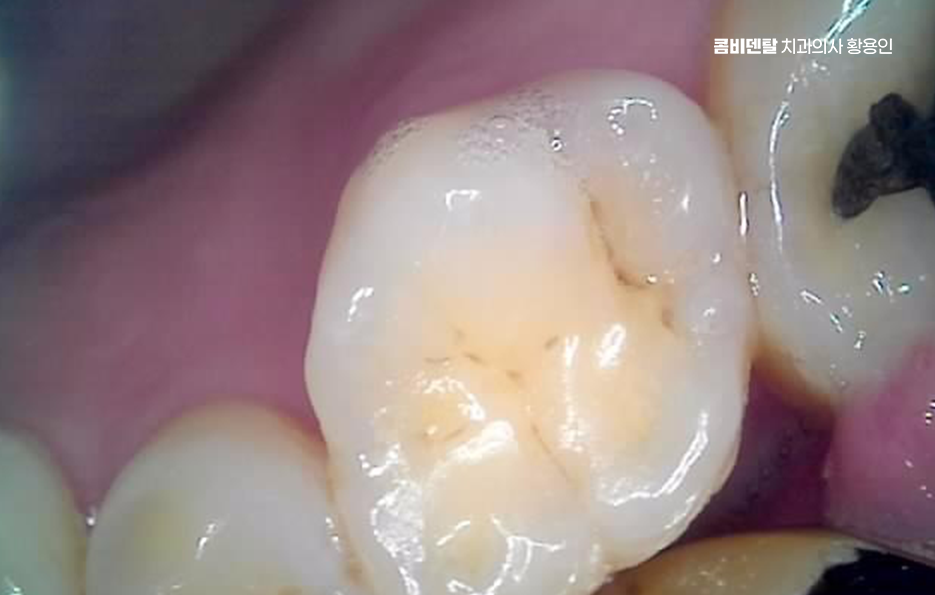

그렇다면 오래된 아말감이나 보철물을 무조건 교체해야 할까 꼭 그렇지는 않으며 현재 상태가 안정적이고, 주변 치아와 잇몸에 문제가 없다면 당장 교체하지 않고 정기적으로 관찰하는 선택도 가능하며 그래서 재치료 계획을 세울 때는 먼저 정확한 진단이 필요하며 겉으로 보이는 상태뿐 아니라, 내부에서 충치가 진행되고 있는지, 치아 구조가 얼마나 남아 있는지, 잇몸과 뼈 상태는 어떤지를 함께 확인해야 하고 이 과정을 통해 단순 교체로 충분한지, 아니면 더 넓은 범위의 치료가 필요한지를 판단하게 될 수 있었어요

아말감을 교체하는 경우에는 단순히 아말감을 제거하고 다른 재료로 채우는 것으로 끝나지 않는 경우도 많은데 제거 과정에서 이미 약해진 치아 구조가 드러나면서, 생각보다 손상 범위가 큰 경우도 있었어요.

이때는 치아를 보호하기 위한 치료가 함께 고려돼야 하며 재료 선택 역시 현재 치아 상태와 씹는 힘, 관리 가능성까지 함께 고려해서 결정하는 것이 좋겠고 재치료 계획을 세울 때 많은 분들이 비용과 시간을 가장 걱정하시는데 물론 중요한 요소이지만, 당장의 부담만을 기준으로 판단하면 오히려 더 큰 치료로 이어질 수 있어요.

결론적으로 오래된 보철물과 아말감의 교체 시점은 문제가 드러났을 때가 아니라, 문제가 커지기 전이 적절한 시점으로 통증이 없을 때 점검하고, 작은 변화가 있을 때 대응하는 것이 치아 수명을 지키는 현실적인 방법이며 오래된 보철물과 아말감을 무조건 불안하게 볼 필요는 없지만 지금 상태를 정확히 알고, 필요한 시점에 필요한 만큼만 치료하는 것, 그것이 오래된 보철물을 현명하게 관리하고 곧 자연치아를 지키는 방법이라 할 수 있어요